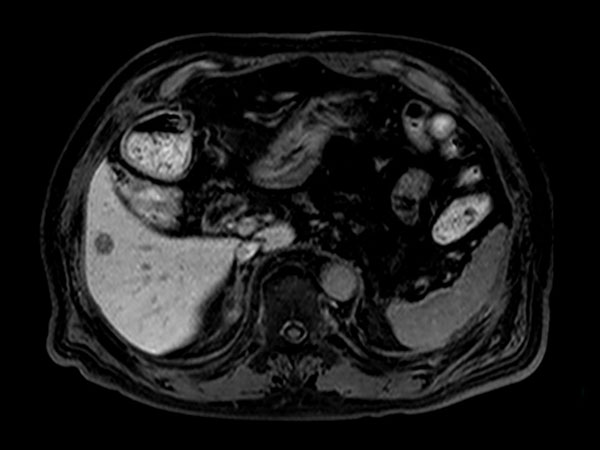

Axial T1w in/out phase